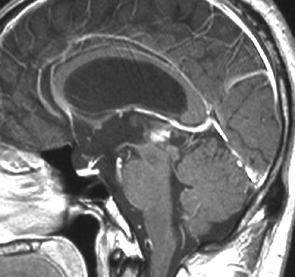

成人女性の松果体細胞腫で充実性腫瘍です。中脳水道が閉塞して軽度の水頭症(頭の中に髄液が溜まる)になってきています。多少凹凸がありますがだいたい楕円形。